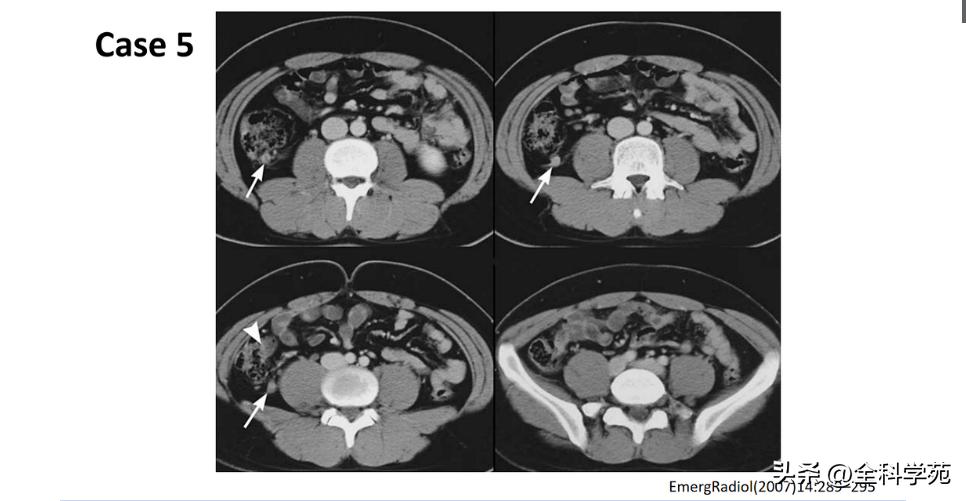

◆ 穿孔 (Perforation)

◆ 局部低强化是穿孔征象

◆ 蜂窝织炎和脓肿 (Phlegmon and abscess